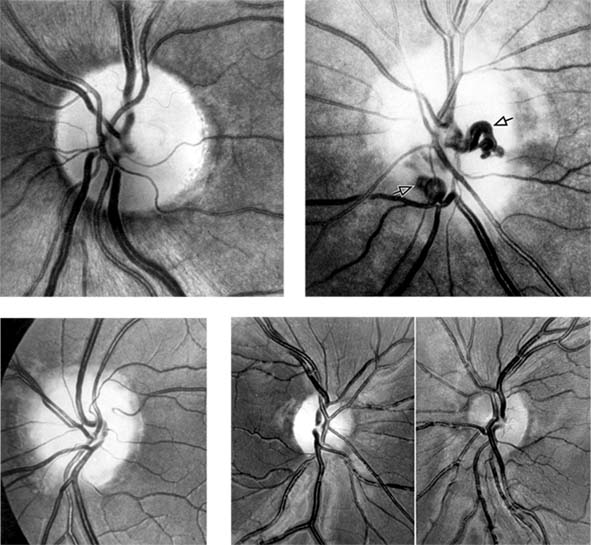

Figure 14-6

Figure 14-6: Examples of optic atrophy. Upper left: Primary optic atrophy due to nutritional amblyopia. Upper right: Secondary optic atrophy with retinochoroidal collaterals (arrows) due to optic nerve sheath meningioma. Lower left: Optic atrophy with optic disk drusen. Lower right: Pallor (atrophy) of right optic disk due to nerve compression by sphenoid meningioma. The left disk is normal.